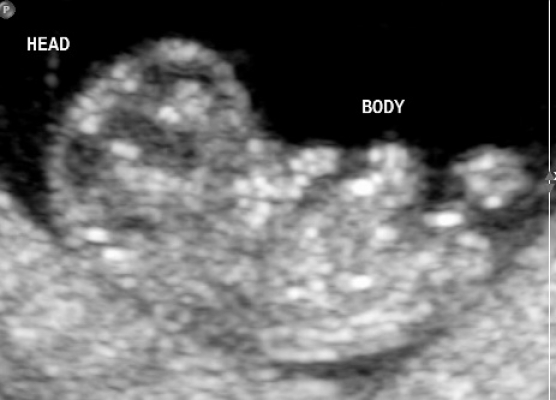

Early Pregnancy Ultrasound

Early Pregnancy Scan

What An Early Pregnancy Ultrasound May Be Able To Detect

• Confirm that your pregnancy is progressing as expected and that the baby is in the right place.

• Check for signs of an ectopic pregnancy (when the pregnancy develops outside the uterus).